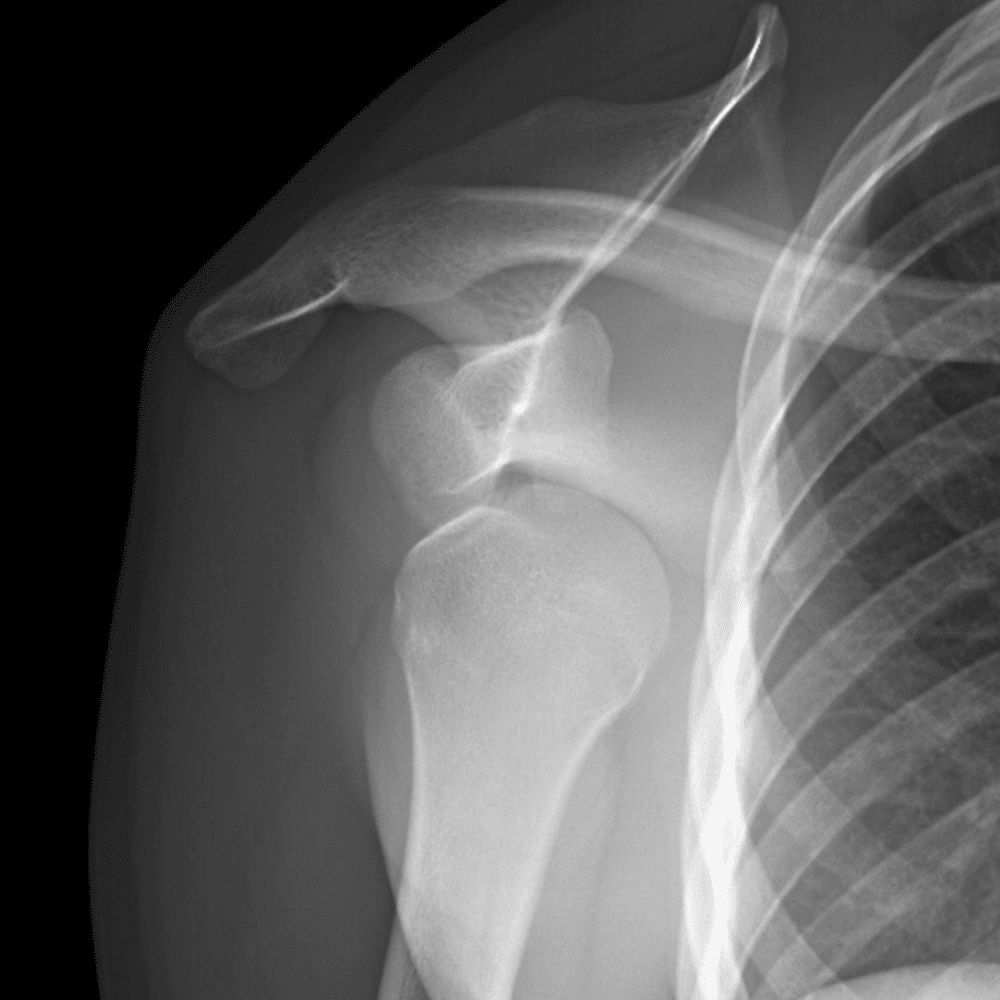

Simuliert den Dienst durch subtile oder schwierige Fälle und einige Normalbefunde.

30 Fälle